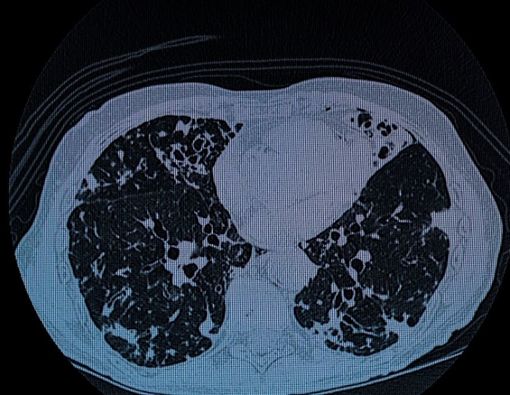

Bronkiektasis merupakan infeksi atau kondisi lain yang dapat melukai dinding saluran udara untuk mencegahnya membersihkan lendir.

Kondisi tersebut akan membuat seseorang mengalami infeksi paru-paru yang serius dan berulang.

“Gejalanya meliputi batuk setiap hari yang terjadi selama berbulan-bulan atau bertahun-tahun. Produksi dahak juga dalam jumlah besar setiap hari,” tambah dr. Theresia.